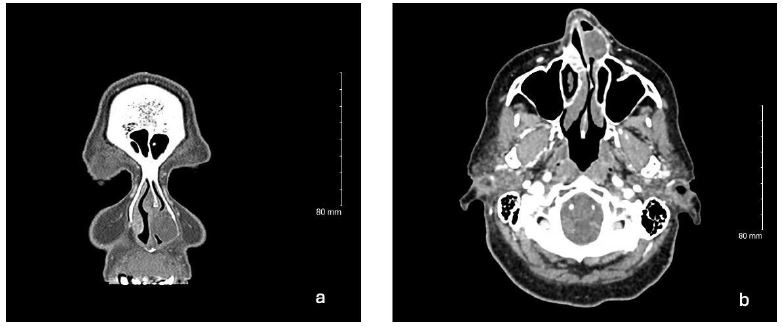

On physical exam, the patient showed normal external nasal landmarks. Anterior rhinoscopy showed intact but deviated nasal septum, and a tan yellowish mass adjacent to the nasal septum with some mucopurulence. Maxillofacial Computed Tomography (CT) scan showed a homogenous 14 mm by 18 mm left anterior nasal cavity mass involving the anterior aspect of inferior turbinate with mass effect on the nasal septum (Figure 1). The patient was then consented and underwent excision of the left nasal mass with concurrent septoplasty and inferior turbinate submucosal resection. Intraoperatively, the mass was found to be solid in consistency, and was removed in piecemeal fashion to gross total resection. During the post operative period, office nasal endoscopy showed irregular mucosal tissue along the anterior inferior turbinate and nasal floor concerning for residual disease. The patient was then referred to tertiary care for complete excision. Additional resection was performed including partial resection of the inferior turbinate and mucosa lining the anterior inferior nasal septum and nasal floor. Further follow-up 12 months post operatively showed no residual disease or recurrence.

Figure 1: Representative images of coronal (a) and axial (b) Computed Tomography (CT) with contrast Left anterior nasal cavity mass involving anterior inferior turbinate with extension to nasal floor and nasal septum. No gross bony changes.